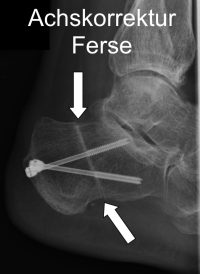

Achskorrigierender Eingriff am Beispiel einer Fehlstellung des Fersenbeins

Eine Fehlstellung des Rückfußes gegenüber dem Vorfuß muss korrigiert werden. Eine Verlagerung oder Verkippung des Fersenbeins kann das Sprunggelenk wieder besser ausrichten und so die Belastungsverhältnisse im Sprunggelenk verbessern. Teilweise ist eine Kombination des Eingriffes mit Korrekturen am Vorfuß notwendig, damit der Patient den Fuß trotz der Stellungsänderung wieder normal aufsetzen kann.